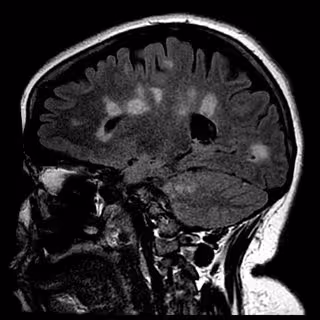

Archivo - Cicatrización del cerebro en la esclerosis múltiple

Archivo - Cicatrización del cerebro en la esclerosis múltiple - UNIVERSITY OF BRITISH COLUMBIA - Archivo